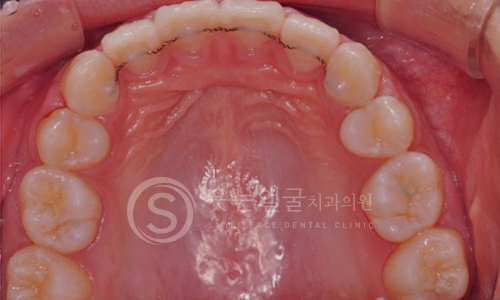

한눈에 보는

임플란트 전후사진